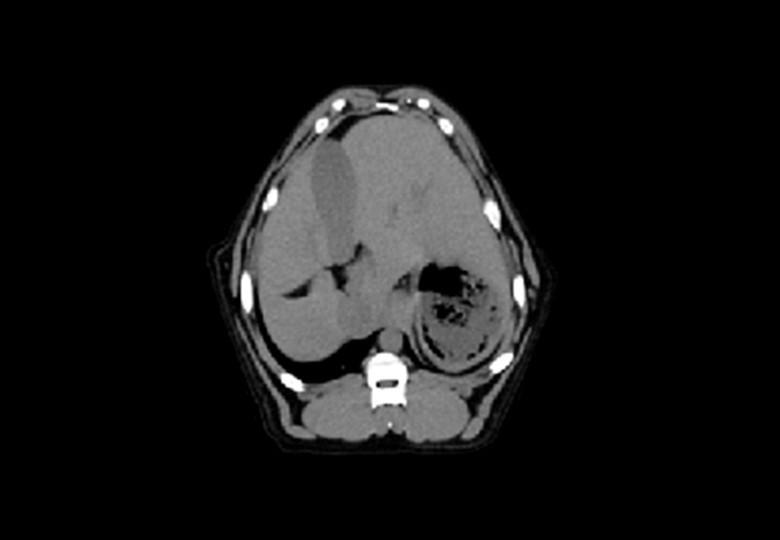

• Abdomen